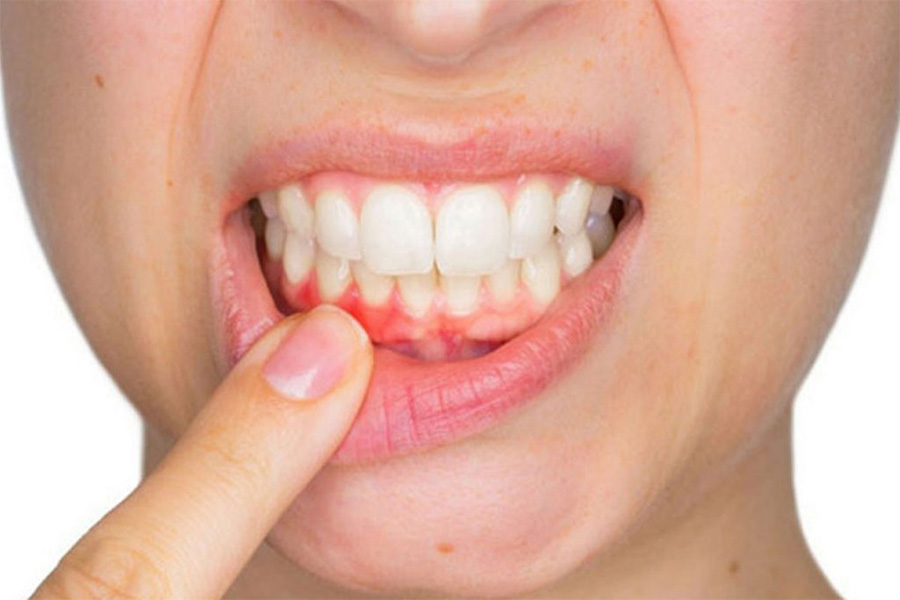

A gengivite crônica é a inflamação da gengiva que, se não tratada, pode evoluir. Ela acontece pelo acúmulo de placa bacteriana. Isso causa vermelhidão, inchaço e até sangramento ao escovar os dentes. Ignorar pode levar a problemas mais sérios, como a periodontite, que afeta os ossos que sustentam os dentes.

A gengivite crônica pode parecer uma coisa pequena, mas se não for tratada, ela pode se agravar e trazer outros problemas. É aquela inflamação persistente que deixa a gengiva inchada e às vezes sangrando. O principal culpado? Acúmulo de placa bacteriana. Pois é, aquela sujeirinha que não sai com uma escovação básica. Precisamos ser mais eficientes na limpeza diária.

Se você notar que sua gengiva está sempre vermelha, sensível ou até mesmo recuando, pode ser gengivite crônica. Não ignore esses sinais! A boa notícia é que, na maioria das vezes, com os cuidados certos em casa e, claro, acompanhamento do dentista, a situação melhora muito. Ele poderá te orientar sobre os produtos e técnicas mais adequados para o seu caso.

Sabe quando a gengiva fica inchada, vermelha e sangra fácil? Se isso já virou rotina, é sinal de gengivite crônica. E olha, ignorar isso só piora o quadro. Muita gente acha que é normal, mas não é. Se você não cuidar, a inflamação pode avançar e virar algo mais sério, como periodontite. Essa é a fase em que o osso que segura seus dentes começa a ser afetado. Ninguém quer chegar nesse ponto, né?

A gengivite crônica se caracteriza por uma inflamação persistente na gengiva, que fica vermelha, inchada e pode até sangrar com facilidade. Muitas vezes, a causa é o acúmulo de placa bacteriana que não foi removida corretamente com a escovação e o fio dental. Quando ela se torna crônica, os cuidados caseiros podem não ser suficientes para reverter o quadro, e a ajuda profissional se torna indispensável.